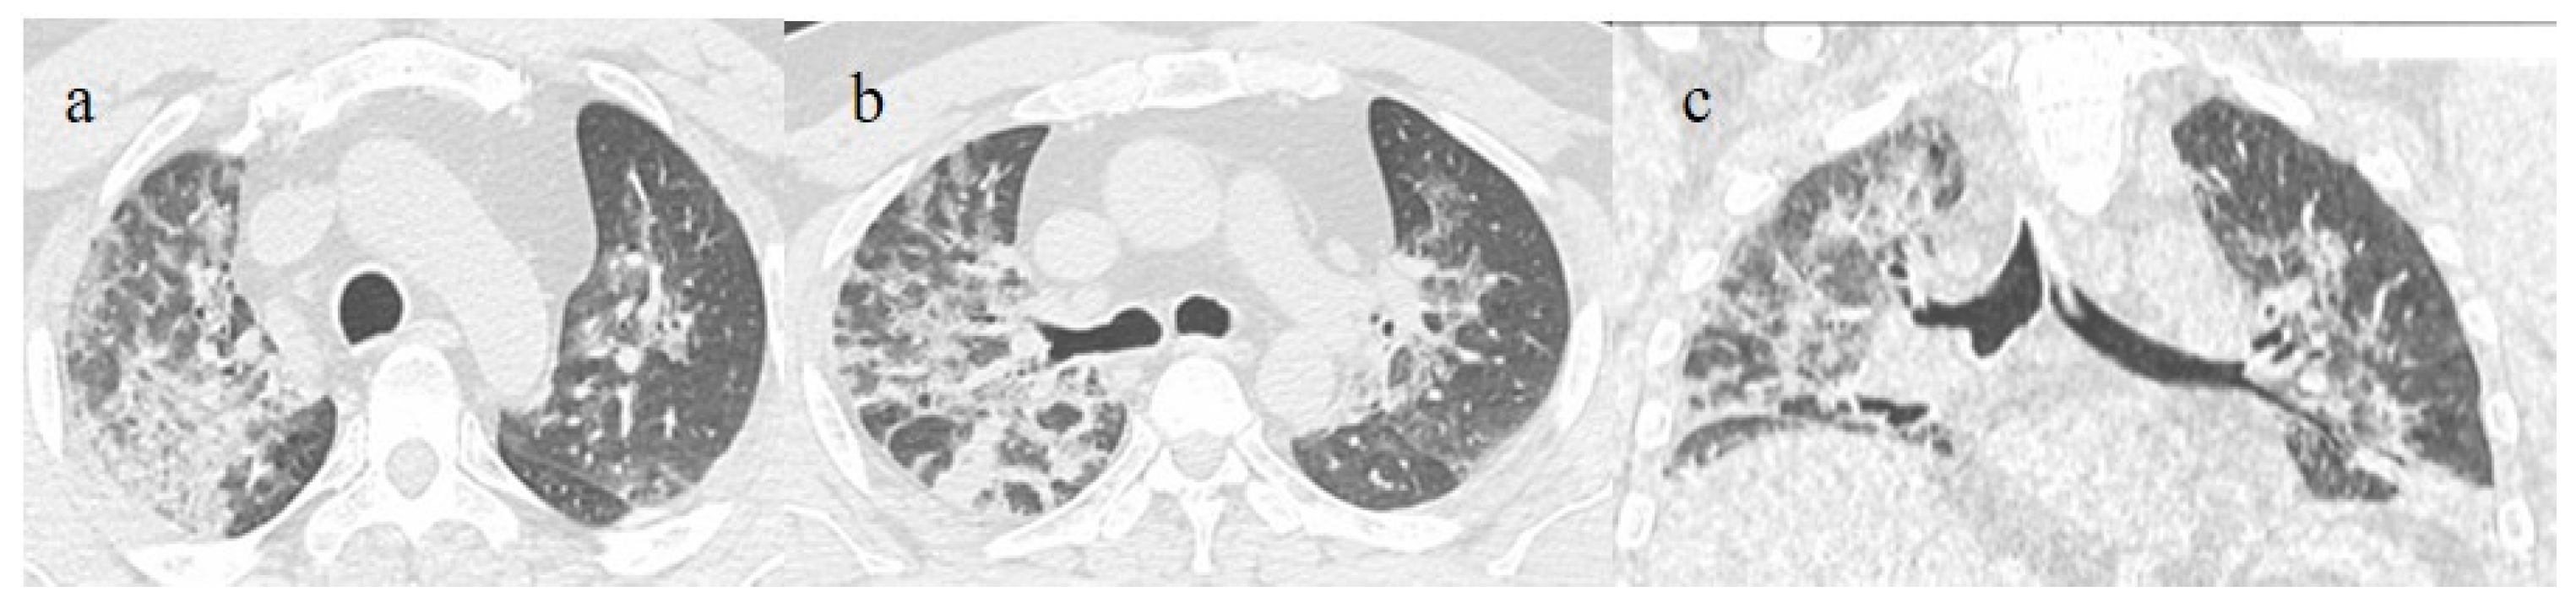

| Typical Appearance | GGOs with a crazy-paving pattern and consolidations in a peripheral and posterior or central-peripheral distribution; multilobar involvement; vascular enlargement, the halo and reversed halo sign; subpleural and parenchymal bands; and architectural distortion. They were predominant since the Delta wave. |

| Typical findings of interstitial pneumonia with peripheral or peripheral central distribution from the wild/type variant since Delta variant |

| Absence of pneumonia or atypical findings during the Omicron wave | |||